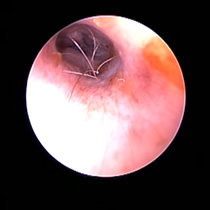

角化症、脂漏症という生まれつきの体質を持ったワンちゃんは耳垢が多くなりがちです。また、角化症、脂漏症の長毛種となれば、耳の中に毛が生えた犬種も多く耳道から耳垢を排泄しにくくなります。それらが原因で耳に汚れがたまります。また長毛種はトリミングに行く回数も多く、耳を洗う機会が多くなります。こんな負の連鎖があり、いずれも耳を悪くする大きな原因になります。その全ての要因に対処しなければ耳の病気は解決しません。写真は鼓膜手前に耳垢や毛が蓄積し、通常の耳洗浄ではきれいにできない状態です。セカンドオピニオンで来院されるワンちゃんで最も多い病気の1つです。

フレンチブルドックはアトピー性皮膚炎、食物アレルギー、脂漏症、甲状腺機能低下症など皮膚病になりやすい犬種です。さらにフレンチブルドックの耳道はもともと入口がとても広く、鼓膜手前で極端に狭くなっています。もし、これらの皮膚病を発症すると外耳炎が起こりやすくなります。外耳炎が起こると耳垢が溜まり、耳洗浄による耳道刺激があったり、微生物の増殖など負のサイクルに陥ることがあります。さらに耳道周囲の体毛が耳の中に入りやすいため、鼓膜手前に毛が蓄積します(写真)。体毛、微生物が増殖した耳垢、皮膚病の放置といった悪化因子が重なると非常に重度の中耳炎になります。